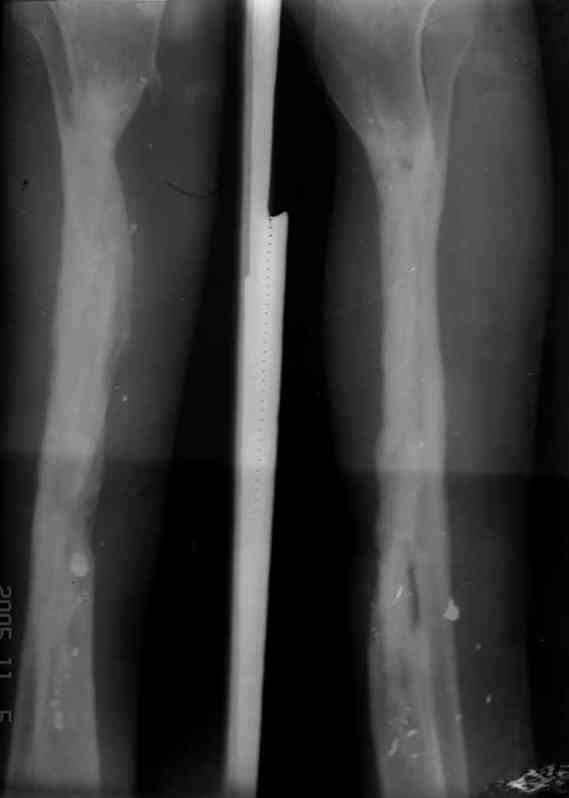

Я думал, что в нижнем отделе голени без мягкотканнего покрытия будет сложно проведения тибиализацию, но твой пример показывает - метод работает даже в таких трудных условиях.

Кстати, как метод использования малоберцовой при дефектах на более высоком отделе большеберцовой, недавно с моим партнерем опубликовали в главе по замещению дефектов в книжке Роберта Росбруха и Светланы Илизаровой по Наружным Фиксаторам.

Правда те мои случаи были сделаны давно, еще в Латинской Америке, и конечно качество исполнения отстает от идеалов, но, несмотря на отсутствие нормальных спиц с упором, метод сработал в свое время.

Приходилось встречать замещенные дефекты малоберцовой костью без применения метода Идизарова, и при соблюдении осторожности хрупкая малоберцовая за короткое время под вождействием нагрузки утолщались в диаметре.